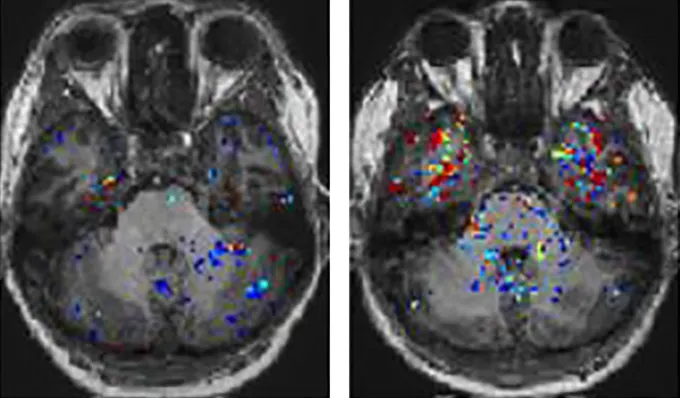

Pacientams, kuriems buvo smegenų migla, atlikus magnetinio rezonanso tomografiją, smegenyse buvo aptikta pažeistų kraujagyslių požymių, vasario 22 d. žurnale "Nature Neuroscience" pranešė mokslininkai. Šių žmonių į kraują įšvirkšti dažai nutekėjo į smegenis ir susikaupė regionuose, kurie vaidina svarbų vaidmenį kalboje, atmintyje, nuotaikoje ir regėjime.

Įšvirkštas dažiklis apšvietė visų dalyvių smegenis atliekant smegenų magnetinio rezonanso skenavimą. Žmonėms, pasveikusiems nuo COVID, dažiklis sunkiai prasiskverbė pro smegenų kraujotakos barjerą. Taip pat ir ilgai COVID sergančių pacientų, kuriems nebuvo smegenų miglos, atveju dažiklis dažniausiai likdavo vietoje, uždaromas kraujagyslėse. Tačiau aštuonių iš 11 dalyvių, kuriems buvo smegenų migla, dažiklis buvo linkęs pasišalinti iš kraujagyslių ir patekti į smegenų audinį.

Piešinys: Ilgą laiką COVID sergantiems pacientams, kuriems yra smegenų migla (smegenų skenavimas dešinėje), į kraują sušvirkšti dažai linkę nutekėti į smegenis (žr. spalvotas dėmeles) labiau nei žmonėms, kuriems nėra smegenų miglos (kairėje).